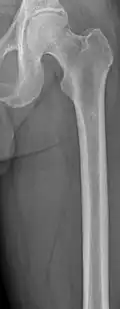

The diagnostic examination of a person with suspected multiple myeloma typically includes a skeletal survey. This is a series of X-rays of the skull, axial skeleton, and proximal long bones. Myeloma activity sometimes appears as "lytic lesions" (with local disappearance of normal bone due to resorption) or as "punched-out lesions" on the skull X-ray ("raindrop skull"). Lesions may also be sclerotic, which is seen as radiodense.[76] Overall, the radiodensity of myeloma is between −30 and 120 Hounsfield units (HU).[77] Magnetic resonance imaging is more sensitive than simple X-rays in the detection of lytic lesions. An MRI may supersede a skeletal survey, especially when vertebral disease is suspected. Occasionally, a CT scan is performed to measure the size of soft-tissue plasmacytomas. Nuclear Medicine Bone scans are typically not of any additional value in the workup of people with myeloma (no new bone formation; lytic lesions not well visualized on nuclear bone scan).

Multiple myeloma in the upper arm -

Humerus with multiple myeloma lesions -

Same humerus before, with just subtle lesions